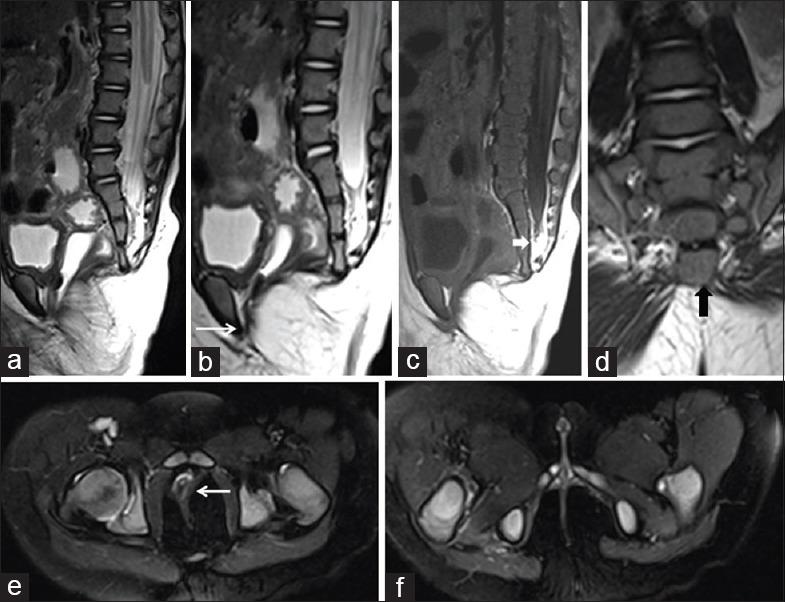

In our study, 21 pediatric patients were diagnosed with sacral agenesis/dysgenesis related to CRS. According to the Pang's classification, 2 (9.5%) patients were Type I, 5 (23.8%) patients were Type III, 7 (33.3%) patients were Type IV, and 7 (33.3%) patients were of Type V CRS. Clinically, 17 (81%) patients presented with urinary incontinence, 6 (28.6%) with fecal incontinence, 9 patients (42.9%) had poor gluteal musculatures and shallow intergluteal cleft, 7 (33.3%) patients had associated subcutaneous mass over spine, and 6 (28.6%) patients presented with distal leg muscle atrophy. MRI showed wedge-shaped conus termination in 5 (23.8%) patients and bulbous conus termination in 3 (14.3%) patients above the L1 vertebral level falling into Group 1 CRS while 7 (33.3%) patients had tethered cord and 6 (28.6%) patients had stretched conus falling into Group 2 CRS.

在我们的研究中,21例小儿患者被诊断为与CRS相关的骶骨发育不全/发育异常。根据庞氏分类,2例(9.5%)患者为I型,5例(23.8%)患者为III型,7例(33.3%)患者为IV型,7例(33.3%)患者为V型CRS。临床上,17例(81%)患者出现尿失禁,6例(28.6%)出现大便失禁,9例(42.9%)患者臀肌发育不良且臀间裂浅,7例(33.3%)患者脊柱上方有皮下肿块,6例(28.6%)患者出现小腿远端肌肉萎缩。MRI显示,5例(23.8%)患者在L1椎体水平以上出现楔形圆锥终丝,3例(14.3%)患者出现球茎状圆锥终丝,属于1组CRS;7例(33.3%)患者有脊髓栓系,6例(28.6%)患者有圆锥拉长,属于2组CRS。